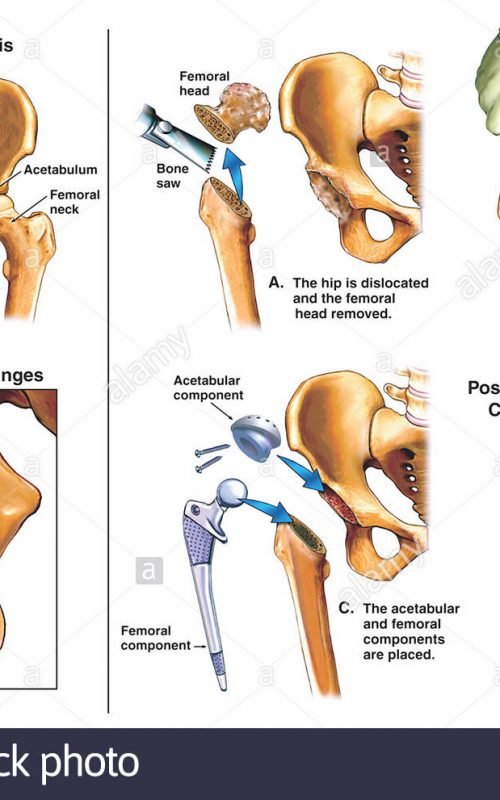

Подготовка к замене тазобедренного